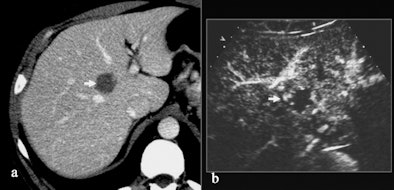

| Hemangioma with atypical enhancement on CT. (a) Contrast-enhanced CT, transverse plane. A solid lesion (arrow) appearing persistently hypovascular during the different dynamic phases (here represented during the portal-venous phase) is identified on the right liver. (b-d) Contrast-enhanced US after sulphur hexafluoride-filled microbubble injection during arterial (b), portal (c), and late phases (d). The lesion presents with globular peripheral enhancement during arterial phase (b), with a progressive centripetal fill-in during portal-venous (c) and late phase (d). Diagnosis of hemangioma was made after contrast-enhanced US. All images courtesy of Emilio Quaia, MD. |